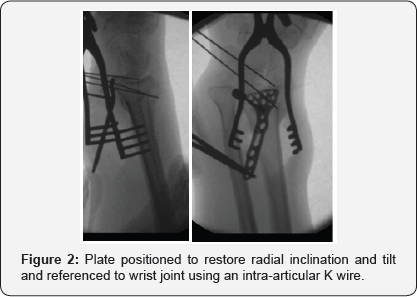

A volar approach to the distal radius extending proximally from the wrist crease along the flexor carpi radialis tendon using a 5-7cms incision, the radial artery identified and protected radially with pronator quadrates elevated along its radial and distal borders and the brachioradialis partially released from its insertion, the volar locking plate of the acumed set was used in all cases (standard size), where the distal end of the plate was aligned with the wrist joint, with the aid of k wires passing through the joint as well as under fluoroscopic image control to align the plate with the required volar tilt and radial inclination, once achieved the distal locking screws were applied. This was followed by the osteotmy being performed as close as possible to the level of deformity, and parallel to the wrist joint, once performed, the radius is pulled out to length with the aid of a laminar spreader applied at the osteotmy site and a cortical screw placed proximally to give the counter pressure required to regain the required radial height and ulna variance. Once corrected the plate was held in place and the first proximal screw was drilled through the oval hole to allow for further fine tuning followed by application of proximal locking screws through the rest of the plate holes (pictures), this was followed by cancellous bone graft harvesting from the same side iliac crest and the amount taken depending on the gap required to be filled at the osteotomy site, cortical bone graft was not added in any of the procedures, the pronator quadratus was brought back to its original position and the subcutaneous layer and skin were sutured using absorbable sutures. All patients had a below elbow well padded splint and discharged the same or the following day to surgery (Figures 1-4).